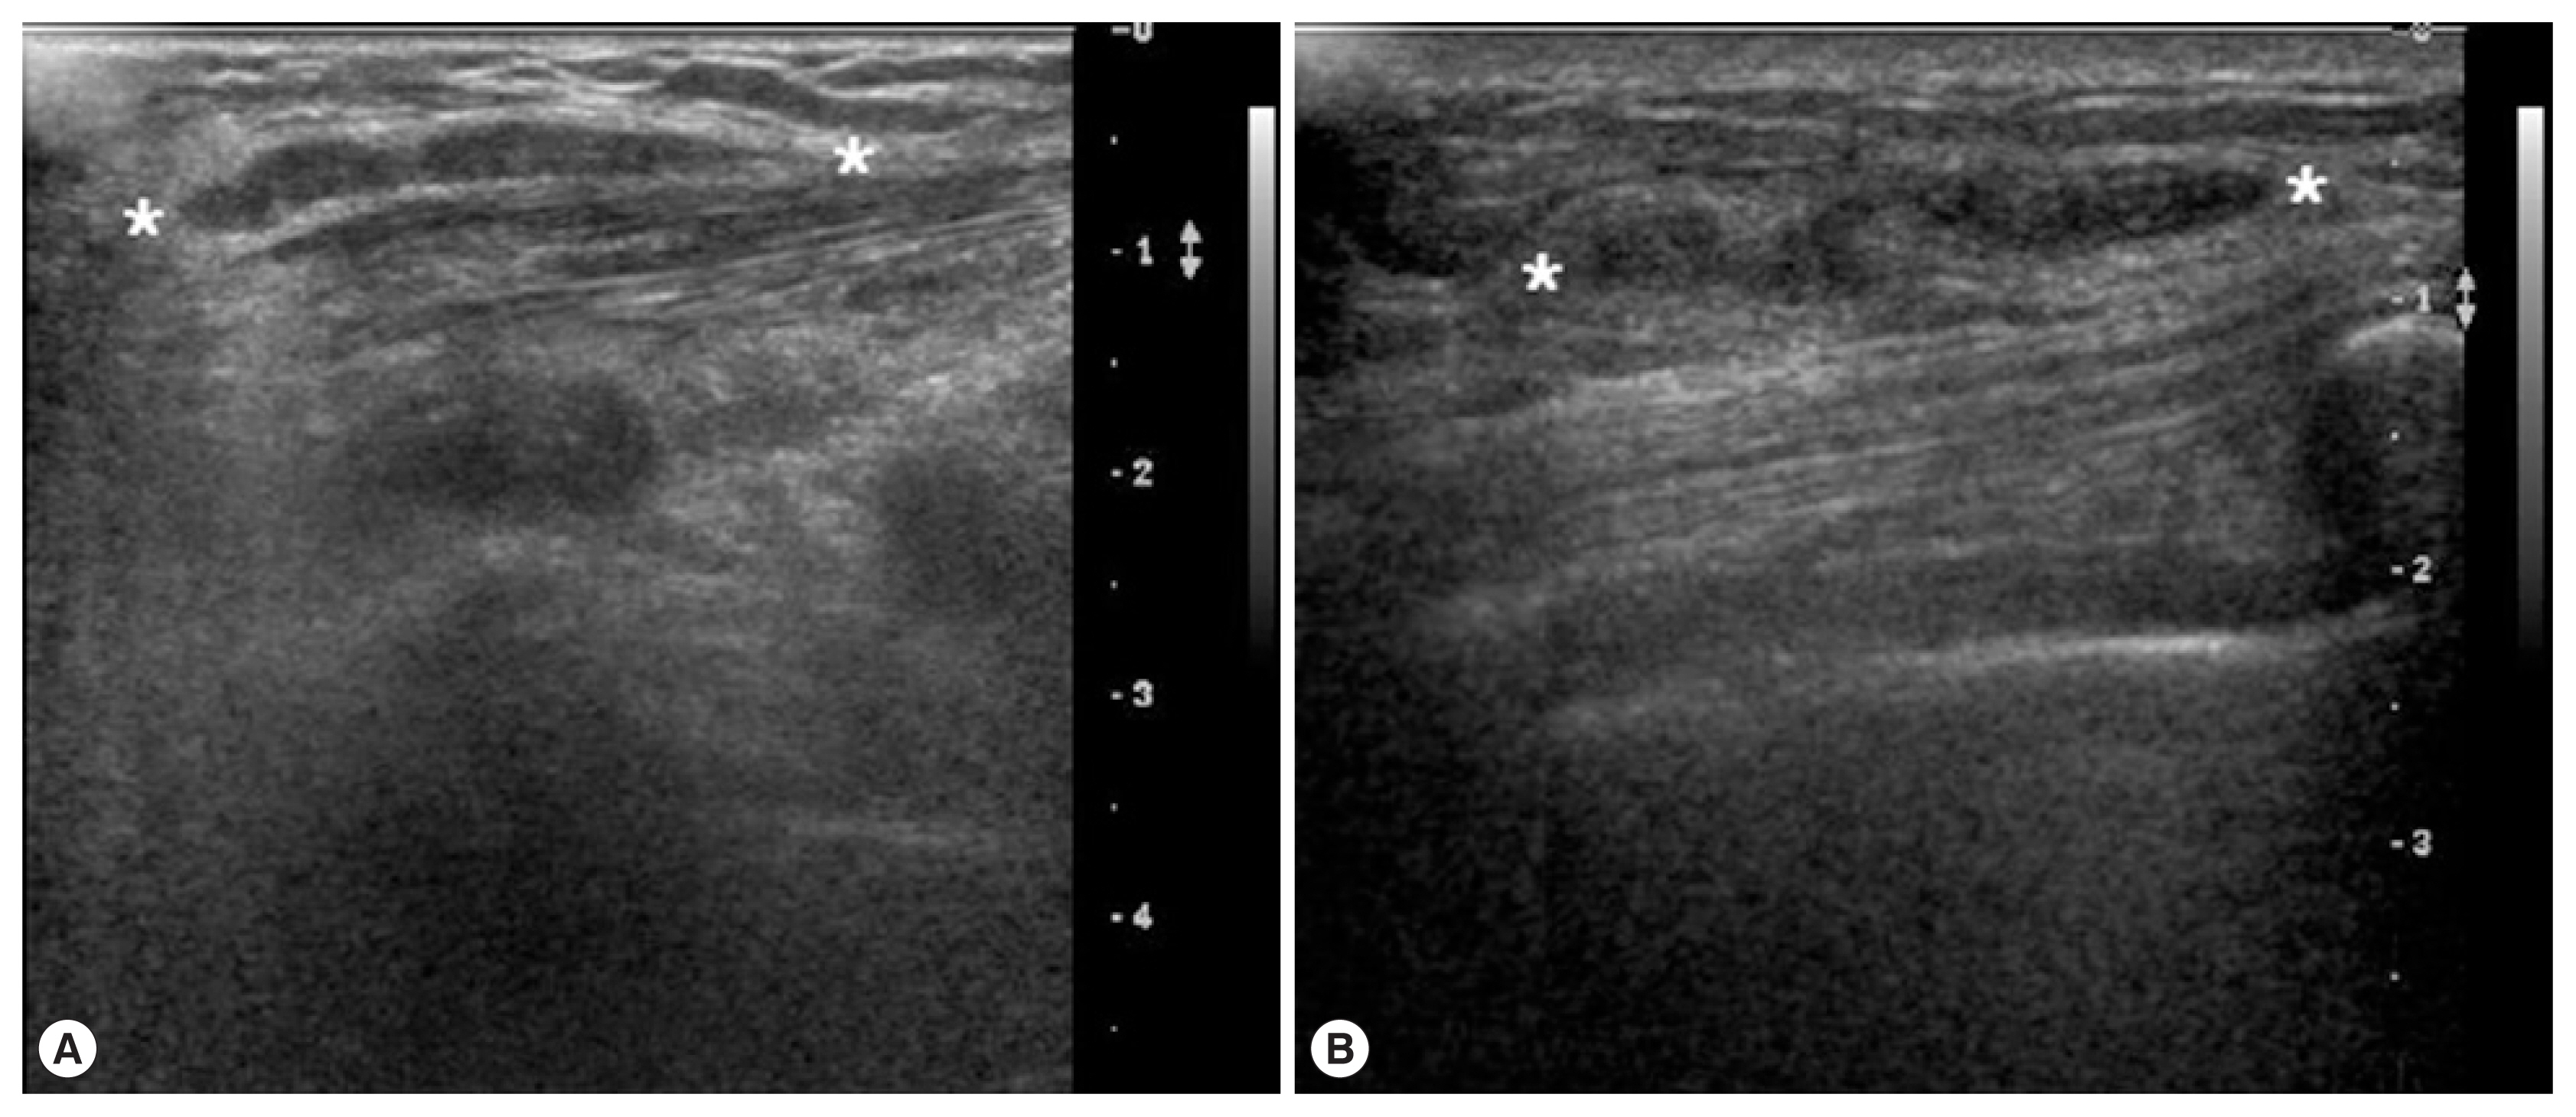

A 69-year-old woman presented with a painless mass of the left upper breast. The mass was palpable 3 weeks prior to presentation. The patient was first treated with acupuncture at another hospital. The patient had no underlying disease other than hypertension. She denied any family history. The patient also denied eating raw foods, including snakes and frogs, although she did enjoy eating Korean-style raw beef from time to time. The patient did not complain of pain or pruritus at the lesion site. Although the mass had been palpable for 3 weeks, it was not palpable 3 days prior to visit. On physical examination, there was no mass found on the breast. There were no specific findings on other parts of the body. Laboratory findings were as follows: hemoglobin of 13.1 g/dl and white blood cell (WBC) count of 6,510/μl (neutrophil 42.0%, eosinophil 5.0%). Chest X-ray and electrocardiogram (ECG) findings were normal. Mammography showed only benign calcifications of the left breast. On breast ultrasonography, a tubular hypoechoic lesion was seen at the subcutaneous fat layer in the left upper outer quadrant of the breast. The tip was connected to the back of the pectoral major muscle (Fig. 1A). A parasitic infection of the breast was suspected, and excisional biopsy was performed. During the operation, a worm surrounded by membranes located between the pectoral muscles was visually identified and removed (Fig. 2). The color of the identified worm was white. Its shape was thin and long, with a length of 30 cm and an outer diameter of 0.3 cm (Fig. 3A). Pathological examination demonstrated characteristic features of sparganum, including tegumental brush border, bundles of longitudinal muscle fibers, and lack of a gastrointestinal tract (Fig. 4A, B). Her postoperative course was uneventful. Follow-up was performed for one month postoperatively. No specific findings were observed.

A 46-year-old woman presented with a painless mass of the right breast. The mass was palpated 4 months prior to presentation. The patient was followed up without any special treatment. She presented to the hospital because of recent increase in size of the lesion. The patient was taking medication for angina symptoms. She had no other underlying diseases. There were no specific findings in her family history. She denied of any recent consumption of raw food. The patient did not complain of pain, pruritus, or other symptoms in association with the lesion. She did not complain of any particular symptoms in other parts of the body. On physical examination, a 2 cm sized painless mass in the right upper part of the breast had grown in size compared to her last visit. The mass was hard and well-defined. There was no visual skin depression or color change. Laboratory findings were as follows: hemoglobin of 11.7 g/dl and WBC count of 5,230/μl (neutrophil 35.5%, eosinophil 3.1%). Chest X-ray and ECG findings were normal. On mammography, there was no specific finding other than an asymmetric hyperdense lesion on the right upper side of the breast. A hypoechoic tubular lesion was observed on breast ultrasonography (Fig. 1B). A parasitic infection of the breast was suspected, and excisional biopsy was performed. During the operation, white circular figures filling the inside of the mass were visible. Length and outer diameter were 16 cm and 0.2 cm, respectively (Fig. 3B). Pathologic examination of the tissue surrounding the worm showed chronic granulomatous inflammation accompanied by necrosis. The worm was confirmed as sparganum and microscopic findings showed characteristic thick eosinophilic tegument, subtegumental calcareous bodies, and longitudinal strips of muscles (Fig. 4C, D). Follow-up was done for up to 13 months postoperatively. No specific findings were observed during follow-up.